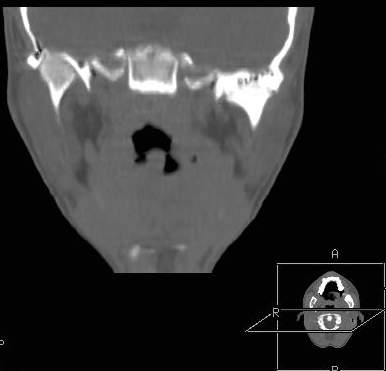

Пациент В., 13 лет. Диагноз: Костный анкилоз левого височно-нижнечелюстного сустава (ВНЧС), левосторонняя микрогения. Болеет с 2-х летнего возраста. Возможная причина развития анкилоза – воспалительный процесс (в первые 1,5 года жизни часто болел простудными заболеваниями, травму родители отрицают). В 3 и 5 лет проводилась редрессация – безуспешно.Прилагаются: ортопантомограмма, кадры СКТ с 3Д реконструкцией. Вопросы: определение тактики лечения – вид и сроки реконструктивно-пластической операции (этапов операции), а именно – неоартропластики и устранения микрогении, медикаментозная терапия в до- и послеоперационный период, ортодонтическое лечение.